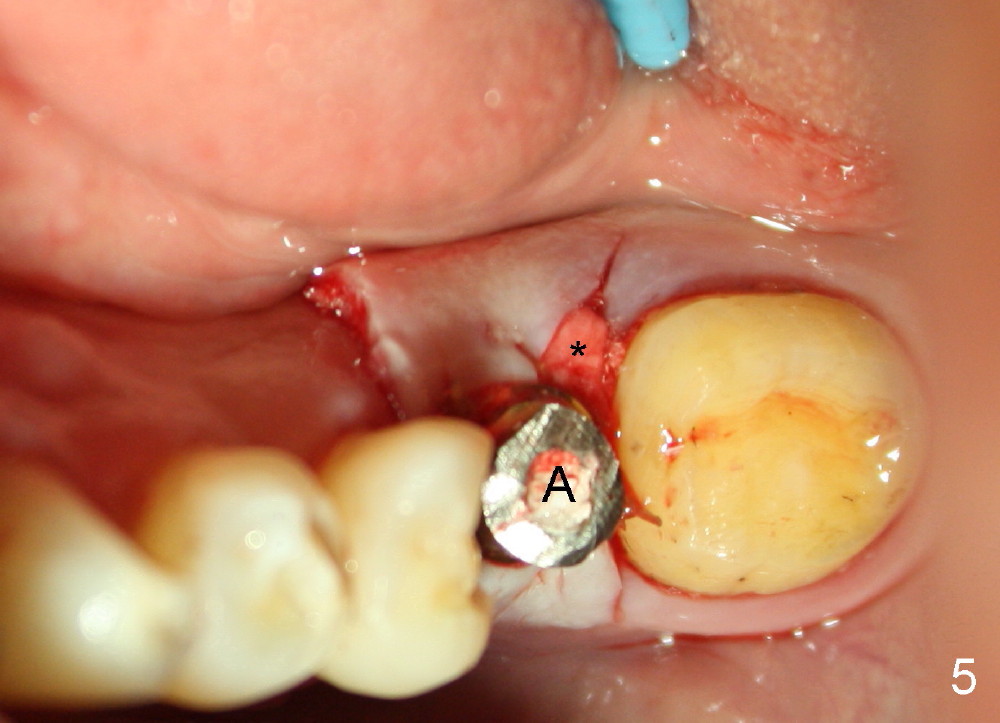

Buccolingually the implant and its straight abutment (5.8 mm, A in Fig.5) are within restorative limit. The most coronal threads of the implant are exposed lingually. Autogenous bone and Osteogen are placed over the threads, followed by collagen membrane (*). The wound is covered by perio dressing (Fig.6). When the wound heals 1-2 weeks postop, the implant will be used to load the provisional fixed prosthesis, which is also supported by #18 and 20 (distal inlay prep: Fig.1 *).